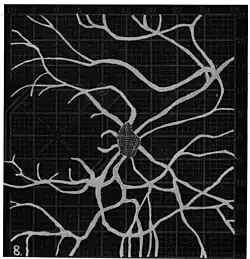

Angioscotomas were first discovered and mapped out by John Norris Evans (1891-02-28--1953-04-08)[2] in 1926, who coined the term angioscotometry to describe the painstaking charting of the scotoma of the retinal blood vessels by manual perimetry. He seated each subject in a seat in a dark setting, and tested whether they could see a tiny bright test object placed at various locations.[3] Using a 1.5 mm white disk, Evans reported intricate branch‑like scotomas that mirrored the arteries and veins emerging from the optic disc, with a full map requiring up to 2 hours to complete. He plotted this for subjects under various conditions, such as while holding breath, with glaucoma, etc. A year later, he confirmed that only short stump‑like scotomas had been noticed previously, some further data plotted with a smaller 1 mm stimuli, and under varying conditions on the subject.[4] He published a monograph on this in 1938 in which he described its use in assisting diagnosis of various conditions, such as retinal edema, glaucoma, optic neuritis, etc.[5]

In the 1940s there were further developments. Evans reviewed the state of research in 1942.[6] In 1945, Welt designed a portable campimeter and linked the size of both the blind spot and the angioscotoma to retinal arterial pressure.[7] In the same year, Weekers and Humblet published detailed tracings that overlaid vessel photographs onto Bjerrum screen plots, firmly establishing the one‑to‑one correspondence between vascular anatomy and scotoma shape.[8]

Widening of angioscotoma under various conditions (holding head lower than trunk; holding the breath; making digital pressure on the same eye; (a vein) on opposite eye; (an artery) on opposite eye).

Widening of angioscotoma under various conditions (holding head lower than trunk; holding the breath; making digital pressure on the same eye; (a vein) on opposite eye; (an artery) on opposite eye).